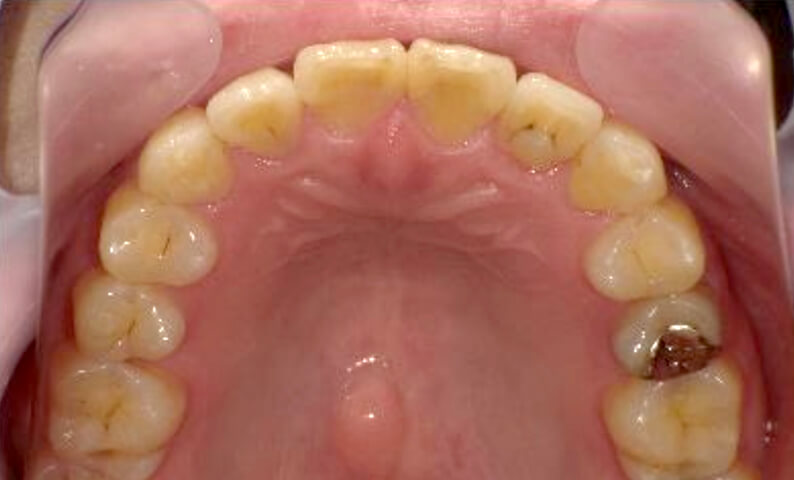

症例_030 上下顎の部分矯正

治療期間:12ヶ月金額:54万円+税女性八の字/V字型捻転歯前歯のガタガタ

| Before | After |

|---|---|

|